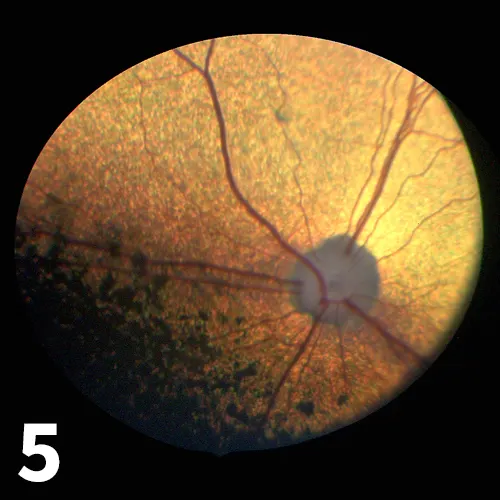

Figure 2

Terminal, progressive retinal atrophy characterized by complete loss of retinal vasculature, a hyperreflective tapetum, and optic disc atrophy in a 12-year-old poodle. At this stage, the animal has no PLR, but some degree of the reflex is usually present in earlier stages of the disease.